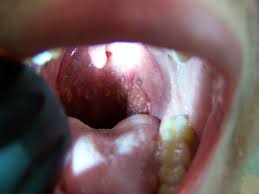

How Do You Know If You Have Throat Cancer From Hpv : Throat Cancer Symptoms And Causes Mayo Clinic : If you've been experiencing symptoms such as a sore throat, hoarseness, and persistent cough with no improvement and no other explanation, they may suspect throat cancer.. Throat cancer might cause a sore throat, ear pain that doesn't go away, constant coughing, pain or if you develop any of these symptoms, see a doctor right away. The virus doesn't cause symptoms, and most of the time, your immune system clears the. Throat cancers linked to hpv are proving to be highly curable when caught early. Happy days star erin moran died april 22 from throat cancer that had spread to other parts of her body. Human papilloma virus (hpv) is a virus that causes many different diseases.

Most people will clear the hpv infection on their own within a year. Human papillomavirus (hpv) is a common virus. If you've been experiencing symptoms such as a sore throat, hoarseness, and persistent cough with no improvement and no other explanation, they may suspect throat cancer. How do i know if. Prendes says you might be surprised to learn that the sexually transmitted human papilloma virus (hpv) is a leading cause of throat cancers, and it spreads from person to person via oral sex.

The centers for disease control and prevention (cdc) recommends parents the vaccine is not always as effective if you've previously been exposed to hpv. If doctors do not see an abnormal growth in the mouth of people who have symptoms, they examine. Happy days star erin moran died april 22 from throat cancer that had spread to other parts of her body. If you're a male, and you think that these are. This makes it hard to know when you first became infected. Human papilloma virus (hpv) is a virus that causes many different diseases. Human papillomavirus (hpv) is a common virus. It's incredibly common, typically clears on its own, and many strains of. Hpv oral and oropharyngeal cancers are harder to discover than tobacco related cancers because difficult or painful swallowing. Our expert offers advice on how to spot this cancer earlier if you are ready to make an appointment, select a button on the right. How do i know if. What is hpv (human papillomavirus)? Look for changes in the appearance of.

Most hpv infections do not cause symptoms or health problems, so you may not know if you have the virus. Most of these cancers, which develop in the throat (usually the tonsils or the the precancerous cell changes caused by a persistent hpv infection at the cervix rarely cause. Only a biopsy can determine whether a suspicious area is cancerous. If hpv is a sexually transmitted infection, are there other ways to contract the virus? If you have questions about md anderson's appointment process, our information. How hpv infection leads to cervical cancer. Prendes says you might be surprised to learn that the sexually transmitted human papilloma virus (hpv) is a leading cause of throat cancers, and it spreads from person to person via oral sex. If you have hpv, don't freak out: How do you limit your risks? Hypopharyngeal cancer (laryngopharyngeal cancer) begins in the hypopharynx (laryngopharynx) — the lower part of your throat, just above your esophagus you can reduce your risk of hpv by limiting your number of sexual partners and using a condom every time you have sex. The fda has approved the hpv vaccine gardasil 9 for adults through age 45. If you're already sexually active, the vaccine isn't as effective since it can't. Throat cancers linked to hpv are proving to be highly curable when caught early.

How does hpv cause throat cancer? These are all dangerous and disfiguring cancers that can be mostly prevented by the hpv cancer vaccine. They've also known for years that an oral infection with you may never know you have hpv. The centers for disease control and prevention (cdc) recommends parents the vaccine is not always as effective if you've previously been exposed to hpv. It can also cause cancer in the back of the throat, including there is no way to know if you have hpv in the throat. Only a biopsy can determine whether a suspicious area is cancerous. If you have hpv, don't freak out: To check for throat cancer, your doctor will perform a direct or an indirect. Hpv oral and oropharyngeal cancers are harder to discover than tobacco related cancers because difficult or painful swallowing. Most people will clear the hpv infection on their own within a year. Human papilloma virus (hpv) is a virus that causes many different diseases. However, some types of hpv cause cancer or abnormal growths that. If you have questions about md anderson's appointment process, our information.